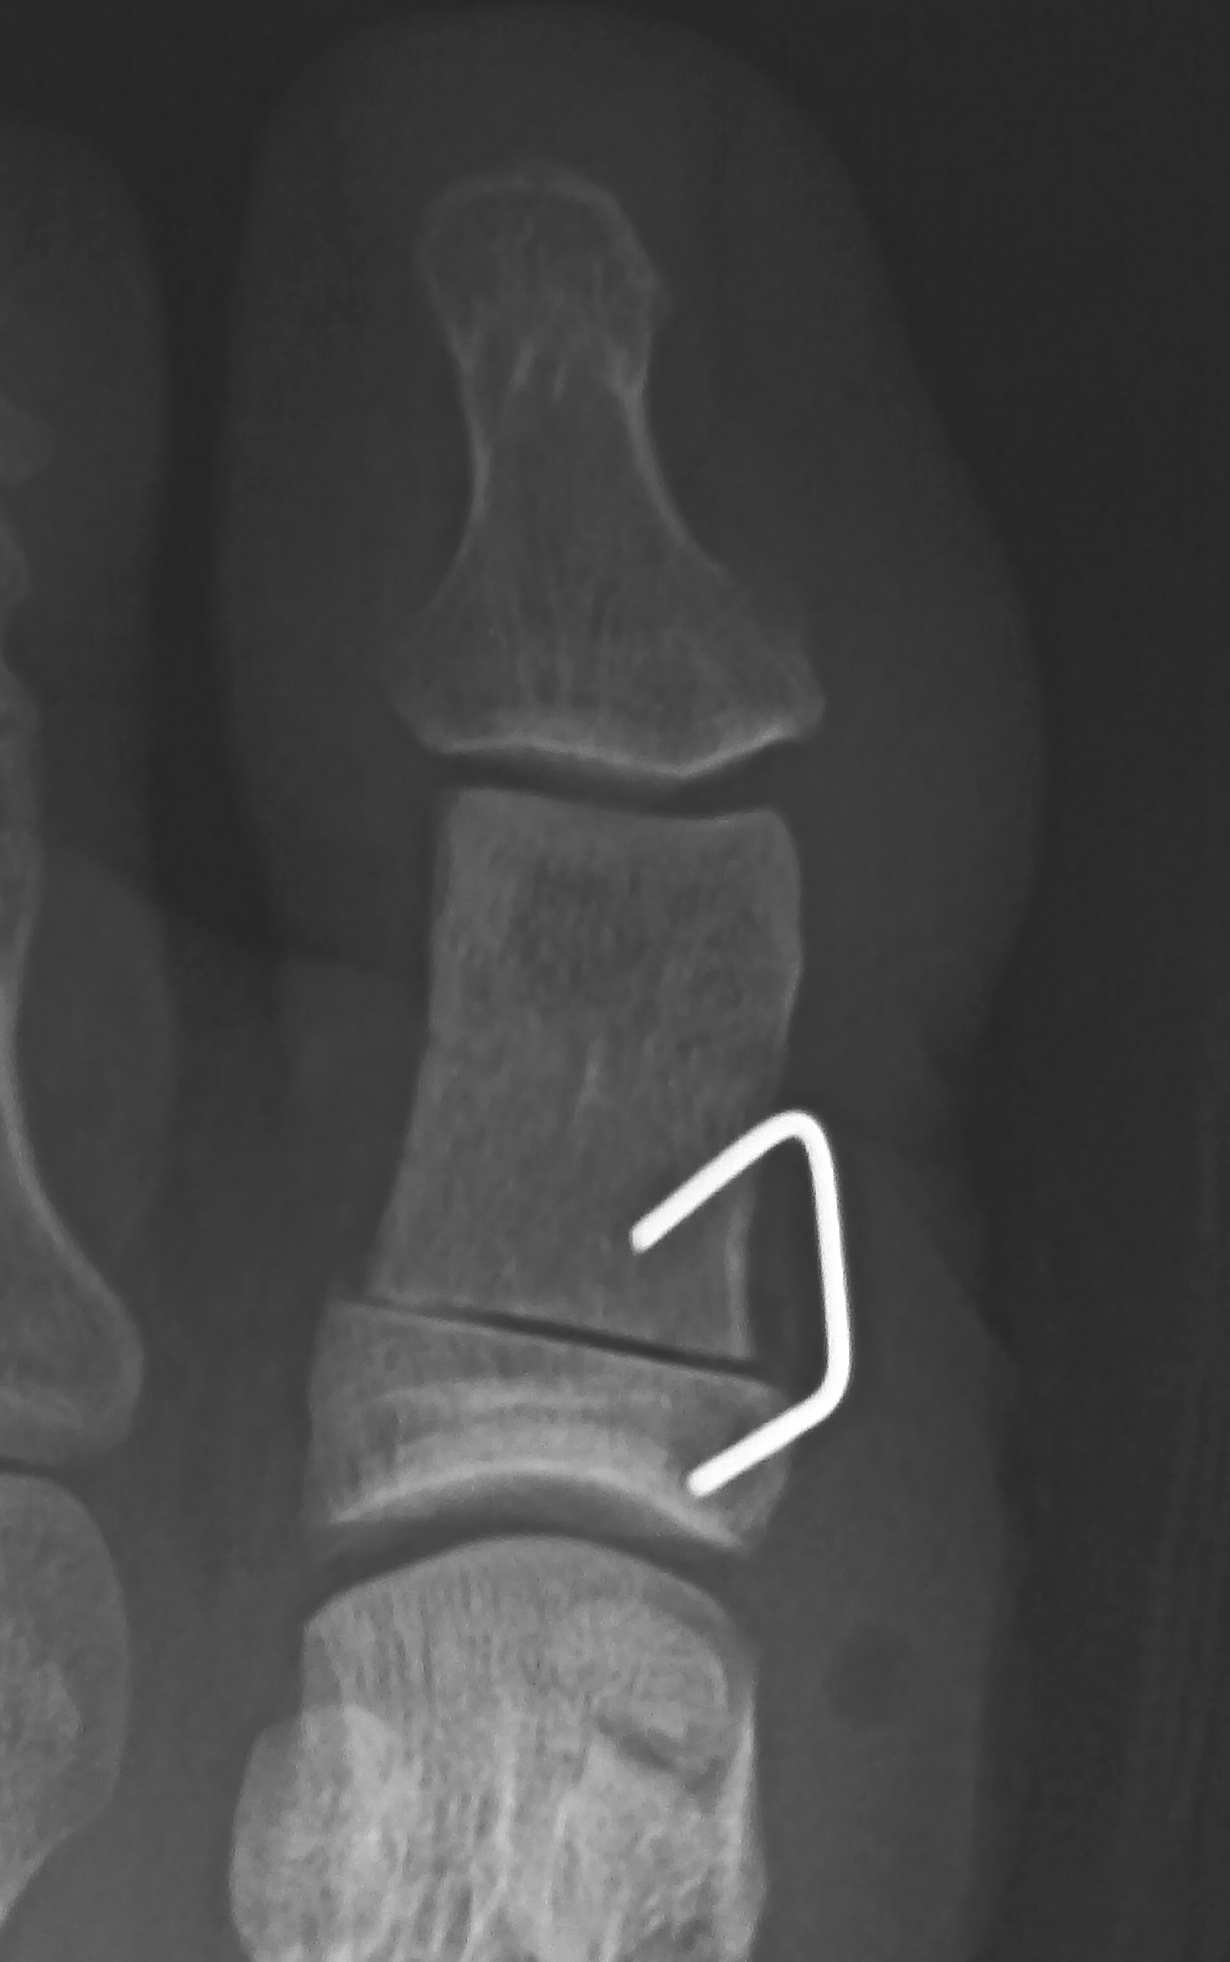

xp_akin_k_wire.jpg エイキン骨切り術ではKワイヤで止める方法も良いが、抜去が必要なので行っていない。

xp_akin_staple.jpg エイキン骨切り術ではステープルで止める方法も良い。しかし、骨癒合した後でもステープルが動いて痛みが出る事があるので、抜去するか、「金属が動くなど、痛みが出たら抜去します。」 と患者に説明しておく。